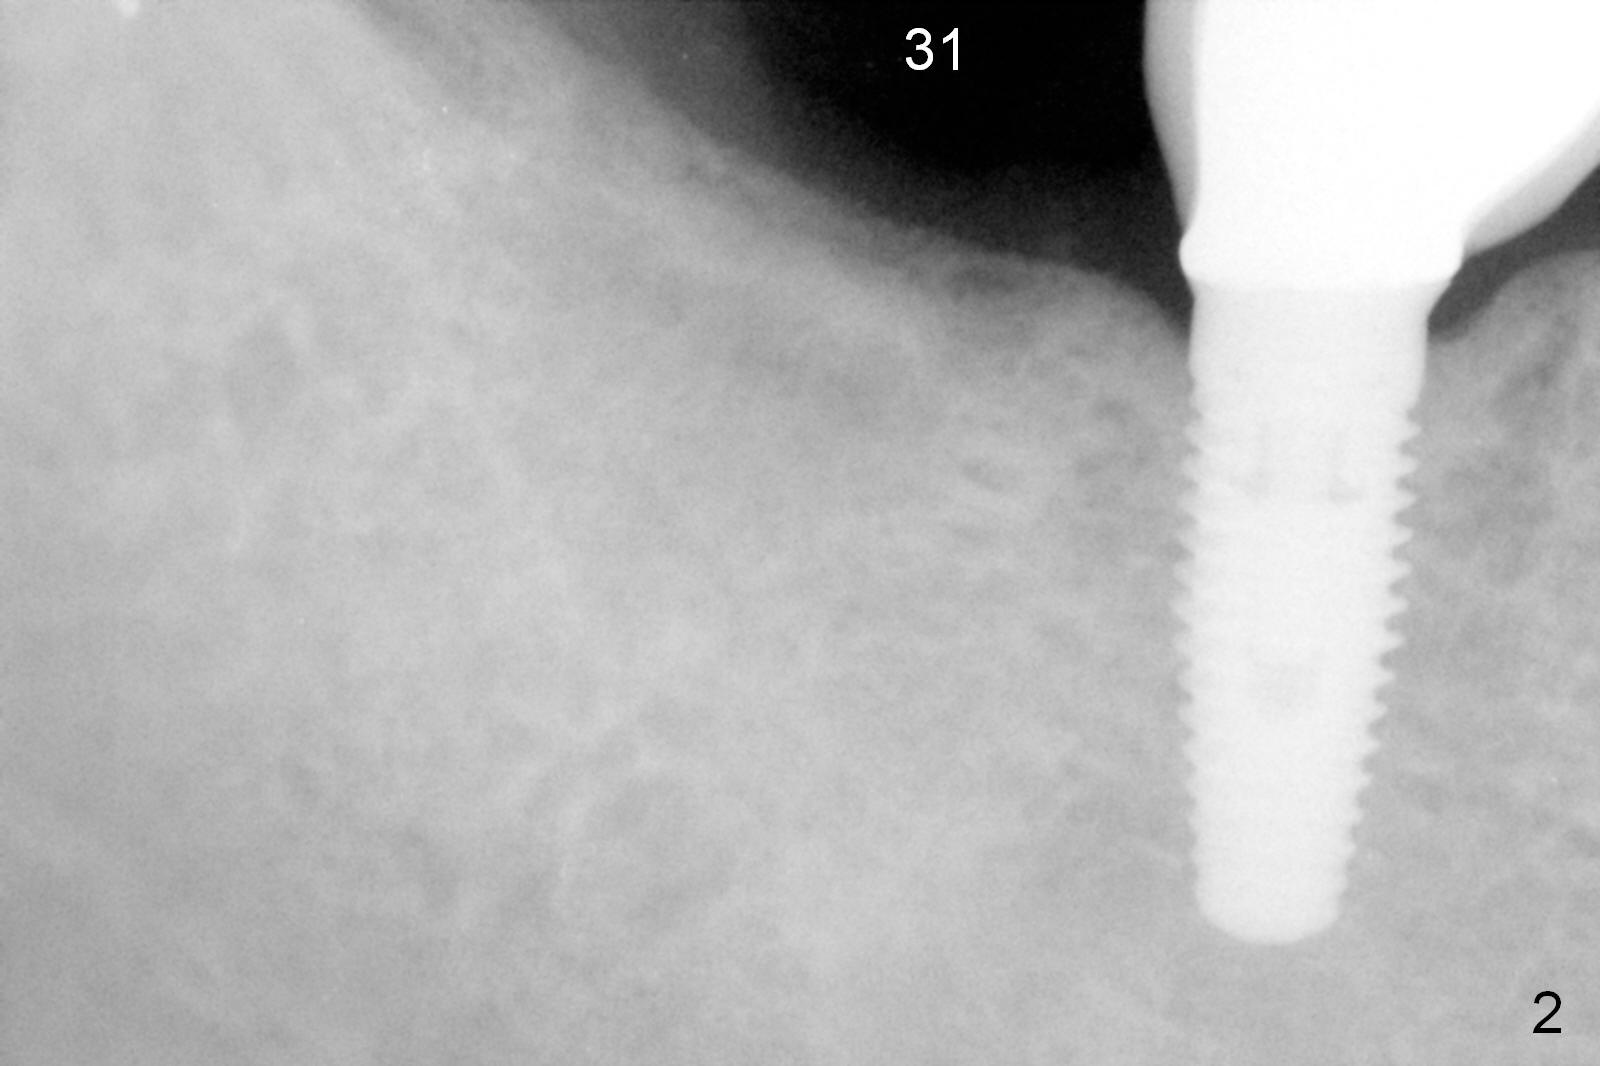

A 62-year-old woman requests #31 implant placement ~ 1 year post extraction (Fig.1). The opposing tooth (#2) appears to have not supraerupted. The socket outline at #31 is visible (Fig.2,3 red dashed line). The initial osteotomy (green) should bisect the socket and be perpendicular to the posterior mandibular slope (pink). The stopper is set at 10 mm with sufficient clearance from the superior border of the Inferior Alveolar Canal (yellow dashed line). Take PA for confirmation and make necessary adjustment. The implant is either 5x17 mm (tissue-level) or 5x13 or 14 mm (bone-level).